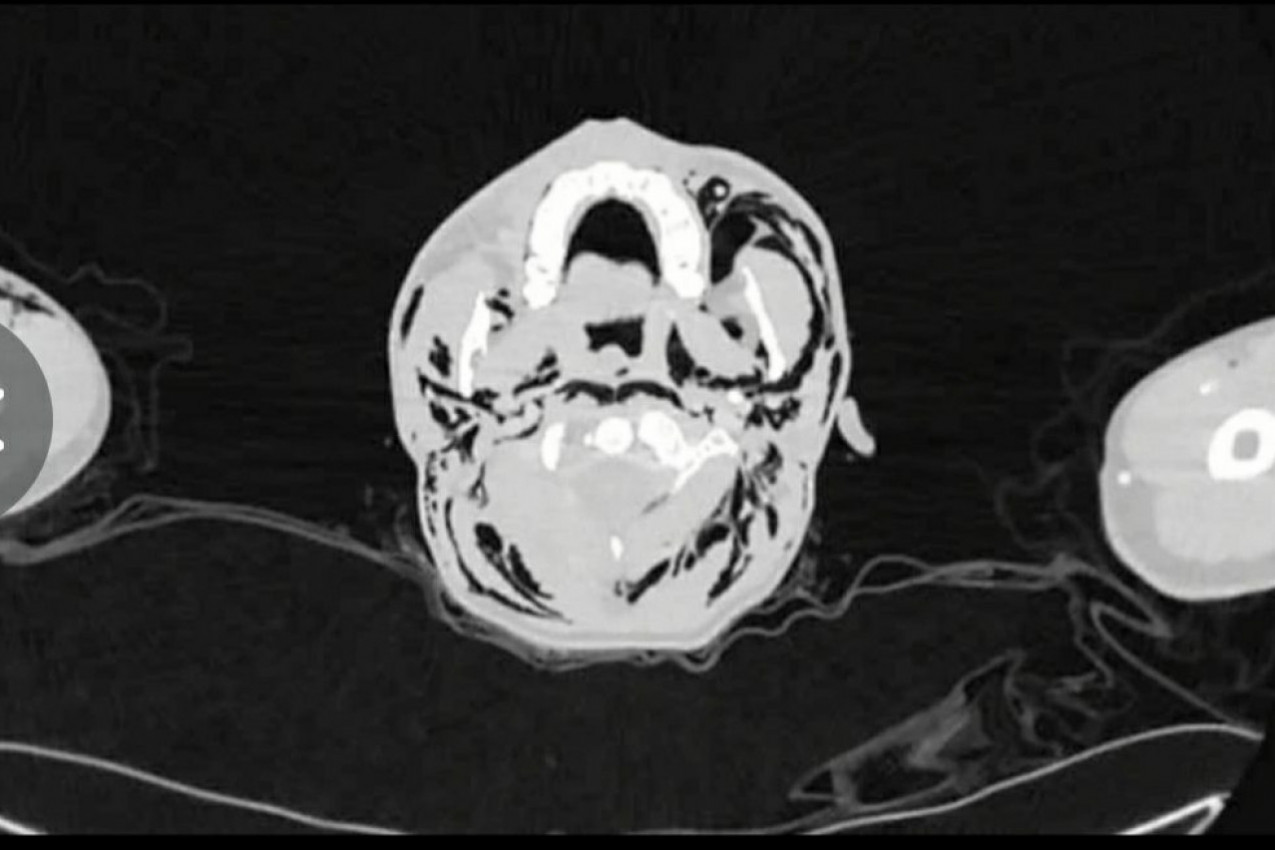

- Pacijentu je dijagnostifikovan spontani pneumomedijastijum (SPM), stanje tokom kog dolazi do "curenja" vazduha iz pluća i njegovog zadržavanja u grudnom košu - prenose mediji i napominju kako je rendgenski snimak upravo prikazao pokazivao zarobljeni vazduh između plućne maramice i grudnog koša.

Prema rečima lekara, ova izuzetno retka komplikacija s plućima najčešće se dešava muškarcima prosečne starosti do 23 godine. Švajcarac je hospitalizovan i dat mu je paracetamol u kombinaciji s drugim lekovima kako bi bolovi i otežano disanje nestali. Interesantno je da je vazduh, koji je mladiću izašao iz pluća, nekako završio i u njegovoj lobanji, što je, takođe, zabeleženo na rendgenu. U ovakvim slučajevima hirurško lečenje je retko.